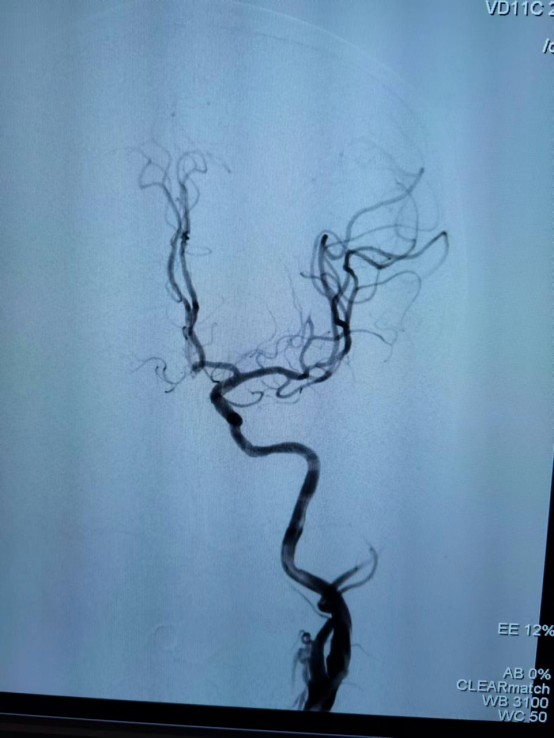

☆ 全脑血管造影是最准确的脑血管造影方法,分辨率是最高的,是诊断脑血管疾病的“金标准”。在临床中,如果通过磁共振血管造影或CT血管造影检查,考虑有脑血管疾病的情况,特别是需要进一步治疗的时候,往往还是需要通过脑血管造影检查最后明确诊断,有些血管疾病在行脑血管造影检查的同时还可行介入治疗。

脑脑血管造影是一种常规的、成熟的诊断方法。脑血管造影的方法是在病人的大腿或手臂穿刺动脉,通过股动脉或桡动脉放置一动脉鞘,通过该动脉鞘将一细而柔软的导管置入所要显示的脑动脉,注入含碘造影剂,同时连续拍照,记录造影过程,通过DSA检查,我们能够准确地了解血管病变的数目、位置、大小、形态,以及与周围血管的关系;也可初步预测或了解疾病的发展,如出血的风险、梗塞的风险等;是否需要进行干预,怎么干预等等。